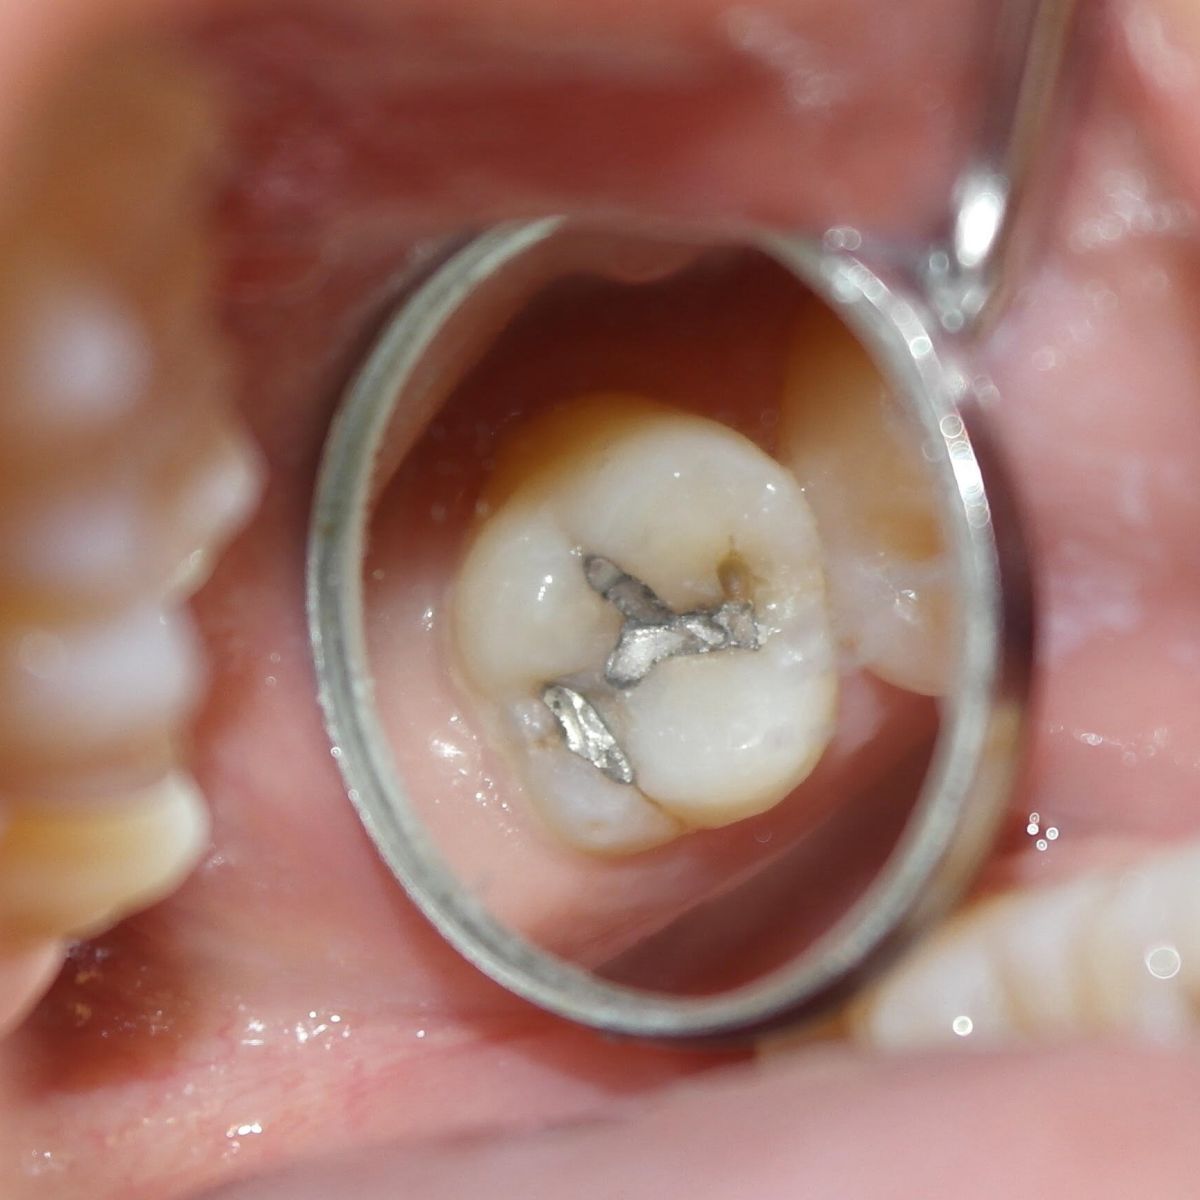

A fogászatban tömés alatt azt a műveletet értjük, mely során különböző anyagok fogba helyezésével helyreállítjuk a sérült fog egységét. A fog tömése fúrással kezdődik, amikor is a fogorvos feltárja a szuvas részeket, és megtisztítja az érintett részeket. Az így keletkezett lyukat tölti ki a fogtömő anyaggal.

Töméskor tehát a szuvas részt mindenképpen el kell távolítani, ezután tömhető be a lyuk, amelyre többféle anyag is használható:

Kisméretű kerámia szemcsék segítségével erősített kompozitból áll, melyek a természetes fogak színével megegyeznek és jó a kopásállóságuk. Legtöbbször fogszuvasodás miatt károsodott fogaknál vagy amalgám tömés eltávolítását követően használjuk. Élettartama általában 10 év.